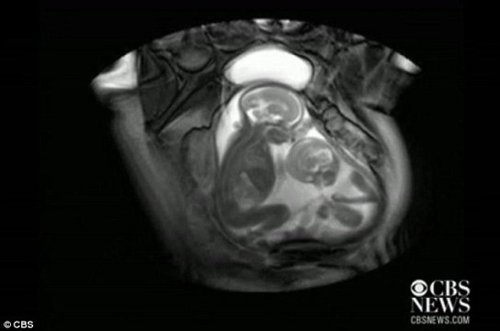

核磁共振成像技術(shù)顯示,一對(duì)雙胞胎在媽媽肚子里拳腳相向“掐架”

中新網(wǎng)12月1日電 據(jù)外媒報(bào)道,近日一段對(duì)孕期20周孕婦的核磁共振的掃描視頻顯示,一對(duì)雙胞胎還在媽媽肚子里就開始揮動(dòng)手腳 “掐架”,令人感到神奇又搞笑。工業(yè)加濕機(jī)

據(jù)報(bào)道,英國倫敦帝國理工學(xué)院(Imperial College)胎兒保健中心本打算用核磁共振成像儀來診斷共享一個(gè)胎盤和同一個(gè)血液供應(yīng)系統(tǒng)的胎兒雙胞胎輸血癥候群(twin transfusion syndrome)情況,卻意外拍到了子宮中雙胞胎的“大戰(zhàn)”。機(jī)房專用加濕機(jī)

視頻顯示,畫面右邊個(gè)子稍小的胎兒在對(duì)左邊稍大的胎兒揮動(dòng)手腳,“拳打腳踢”,似乎打算用身體爭得更多空間。而后者比較安分,也動(dòng)了動(dòng)嘴,縮了一下身子。